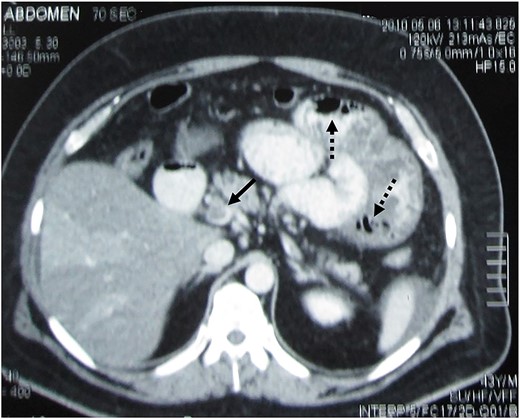

A 42-year-old male with morbid obesity (BodyMassIndex = 44 kg/m2) underwent LSG. On the 17th postoperative day, he was urgently admitted due to severe abdominal pain/diffuse rebound tenderness. Tachycardia (HR = 140/min) and oliguria (<20 ml/h) were also present. Abdominal Computerized Tomography (CT) demonstrated occlusive thrombus at the main branches of the Superior Mesenteric Vein (SMV), air-fluid levels and small-bowel wall edema with intramural gas (Fig. 1). On exploratory laparotomy, two infarcted, small intestinal segments (totaling 150 cm) were identified. Between them, there was a borderline viable loop. We proceeded to resection of the necrotic bowel and construction of two separate stomas. The patient was eventually discharged on home with total parenteral nutrition feeding and LMWH administration (1.5 mg/kg/d) for 6 months. A successful reversal of the stomas was accomplished 5 months later.

Contrast-enhanced abdominal CT demonstrating SMV thrombosis. Black arrow indicates the thrombus inside the vein, whereas the dotted black arrows indicate gas within the small-bowel wall (pneumatosis intestinalis).